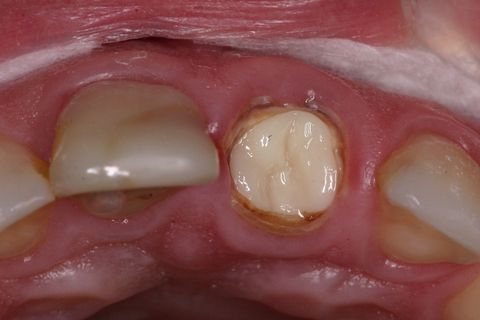

Aspecto Clínico Inicial

Paciente jovem do gênero masculino, apresentou-se à Clínica Integrada do Curso de Odontologia da Universidade Severino Sombra necessitando de um tratamento restaurador no dente 21. Ao exame clínico e radiográfico foi observado uma grande destruição coronária e tratamento endodontico satisfatório (Figuras 1, 2 e 3).